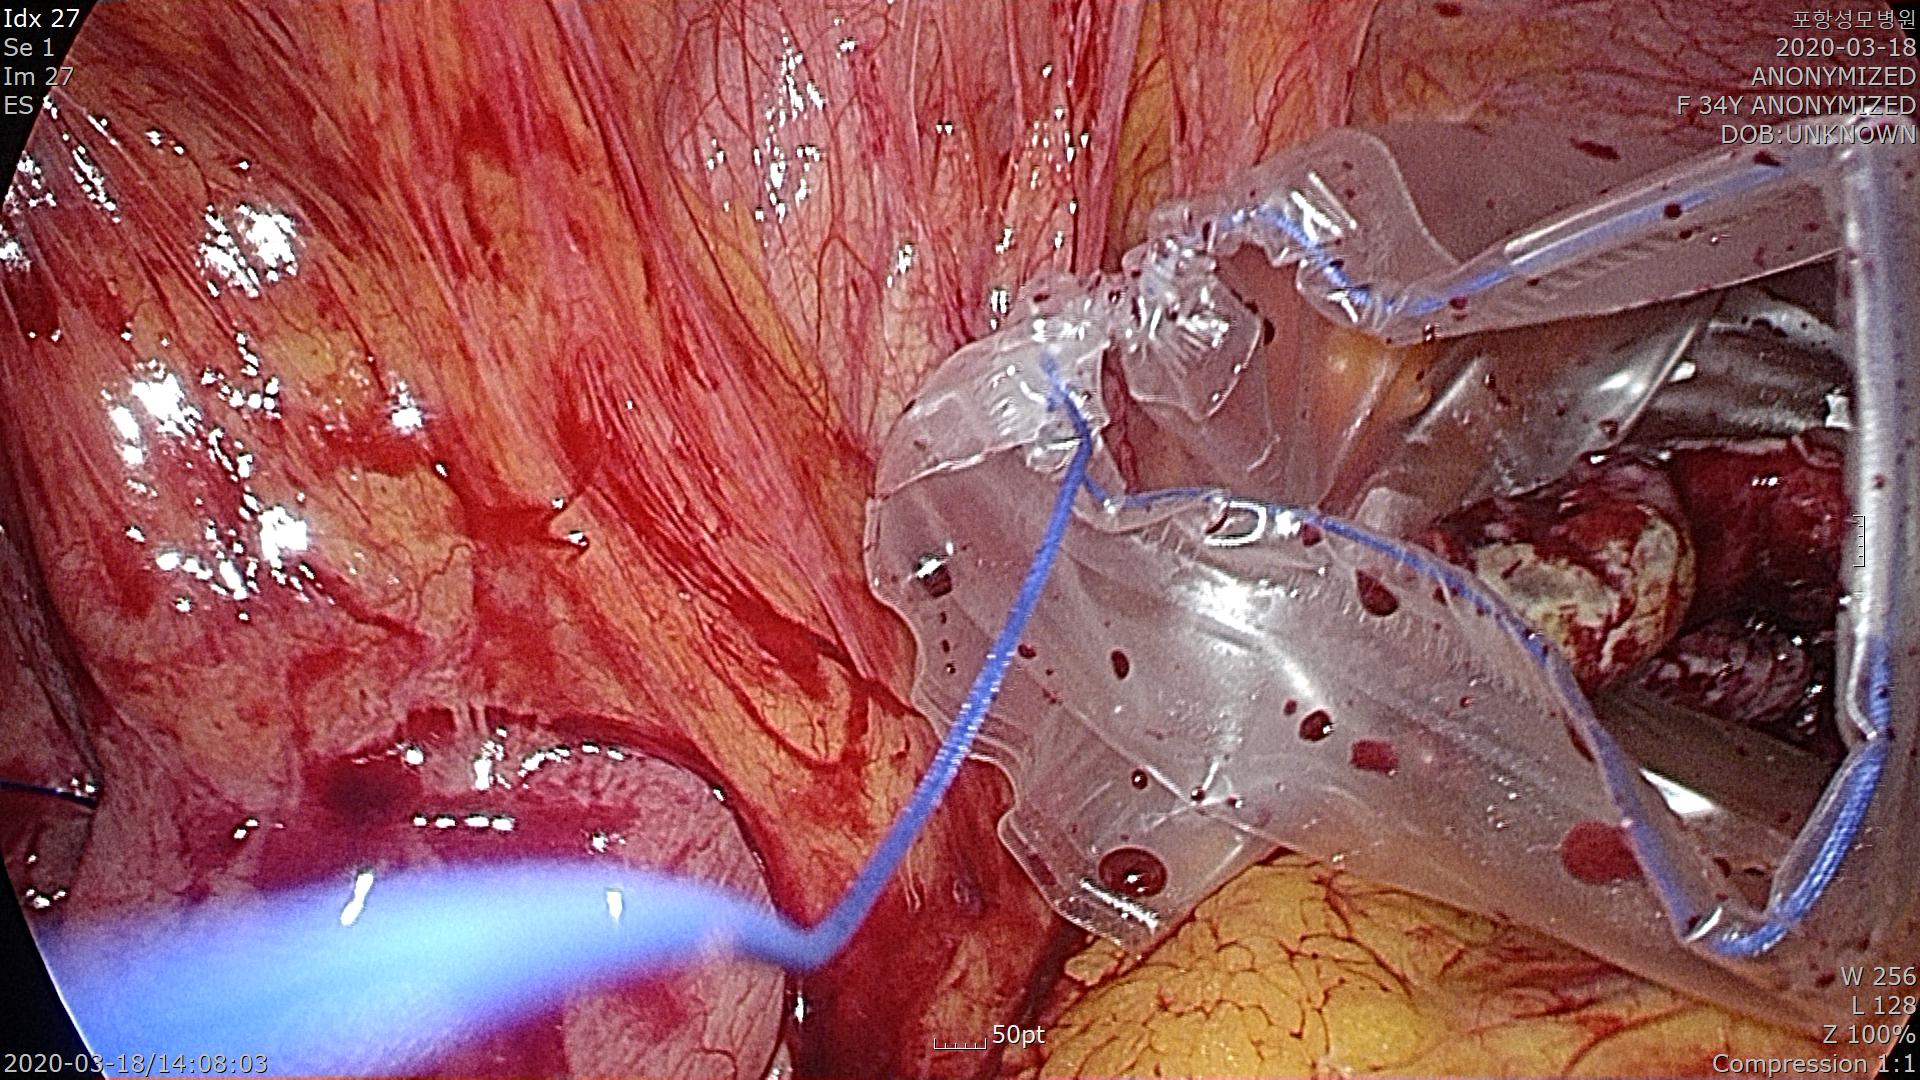

Pouch(비닐봉지)에 담아 복강 밖으로 제거합니다.

충수돌기 기저부의 대장 연결부위가 잘 처리 됐네요.

오염된 복강내를 깨끗히 씻어주고 배액관을 삽입한 후 수술을 종료합니다.